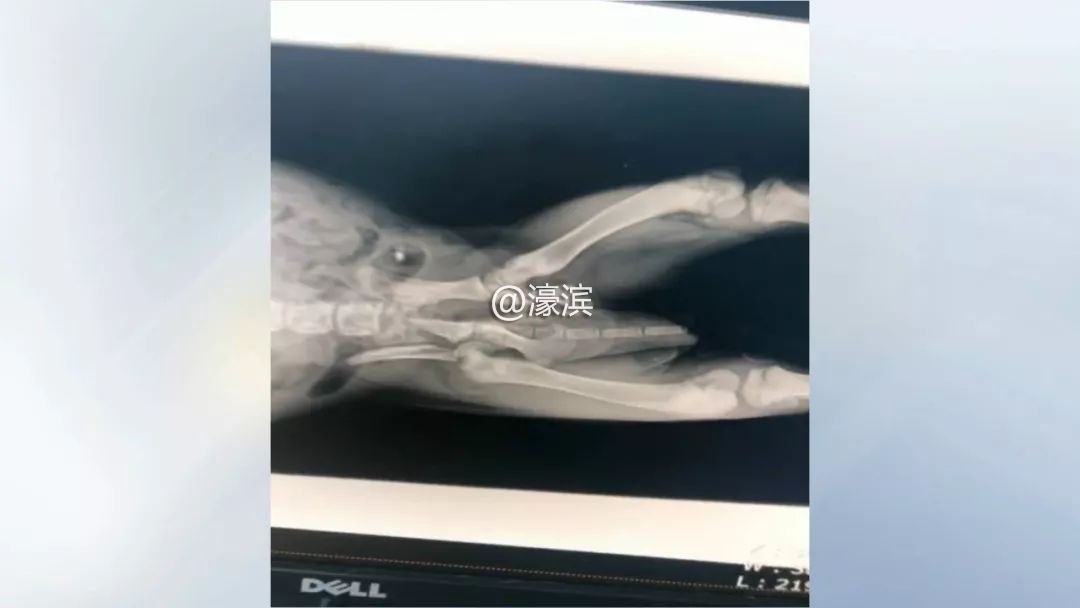

宠物医院负责人 袁嘉:送过来之后检查发现整个盆骨粉碎性骨折,再加上股骨头的断裂,再加上腹腔和胸腔的大面积的内出血。

确诊伤情后,兽医们立即为小狗进行手术。遗憾的是,因为受伤太重,经过大家三个小时的努力,最终还是没能抢救过来。

宠物医院负责人 袁嘉:当我们剖腹探查之后发现,它是肾脏破裂,这就没有办法了,我们大家都已经尽力了。